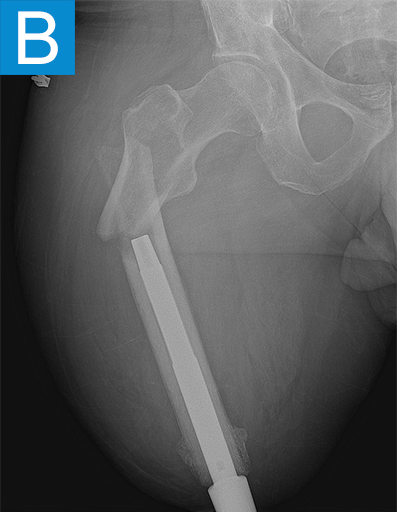

He started progressively loading the implant at 2 weeks and received his full prosthetic leg with simple hinged knee at 6 weeks. At 3 months he no longer used assist devices and at 3.5 months his prosthesis was changed to a microprocessor-controlled knee. Shortly after receiving the new knee, he stumbled stepping over a ledge and fell, sustaining a subtrochanteric proximal femur fracture (Figure 2b). The fracture extended to the tip of the implant, which remained stable in the bone. He underwent open reduction and internal fixation of the femur fracture with a proximal locking plate (Figure 2c). He did not wear the prosthetic leg for 10 weeks, when he began gradually loading the femur. He resumed full weightbearing without assistive devices about 6 weeks later.

Figure 2. Postoperative X-rays shows (A) a femoral osseointegration implant; (B) a subtrochanteric proximal fracture; (C) the femur fracture repaired by open reduction and internal fixation with a proximal locking plate.